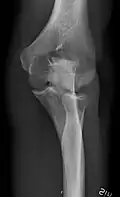

- Knee - AP and Lateral. Intra Condular projections on request

Right knee, anteroposterior -

Right knee, lateral -

Patella, (slightly skew) skyline